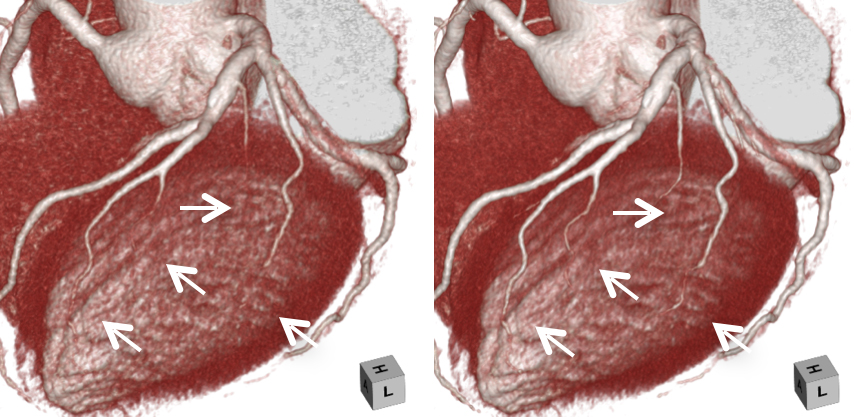

320列CTは、1回転で16cmの撮影が可能なため、心臓を短時間(1秒未満)で撮影することができ、不整脈にも強く理想的な画像が得られます。また、従来より被曝が少ないのも特徴です。 我々は、このCT装置の特徴を最大限に活かした検査を行っています。

高精細画像再構成

当院で稼働中の320列CT装置2台をバージョンアップし、これまで以上の高精細なCT画像が得られるようになりました。

CT装置の解像度は、主にハードウエアの構成に依存するため、それ以上の高精細な画像を得ることが出来ませんでした。しかしながら、近年注目されている深層学習(ディープラーニング)による画像構築技術を用いて、最も高精細なCTで撮影された画像を教師画像とすることで、これまでの解像度を超える画像が得られるようになりました。

キヤノンメディカルシステムズが開発したPrecise IQ Engine(PIQE)によるディープラーニングの画像によって、冠動脈CT検査で評価が難しい石灰化やステントに接する部分の描出が向上されるため、さらに正確な画像診断が可能となりました。